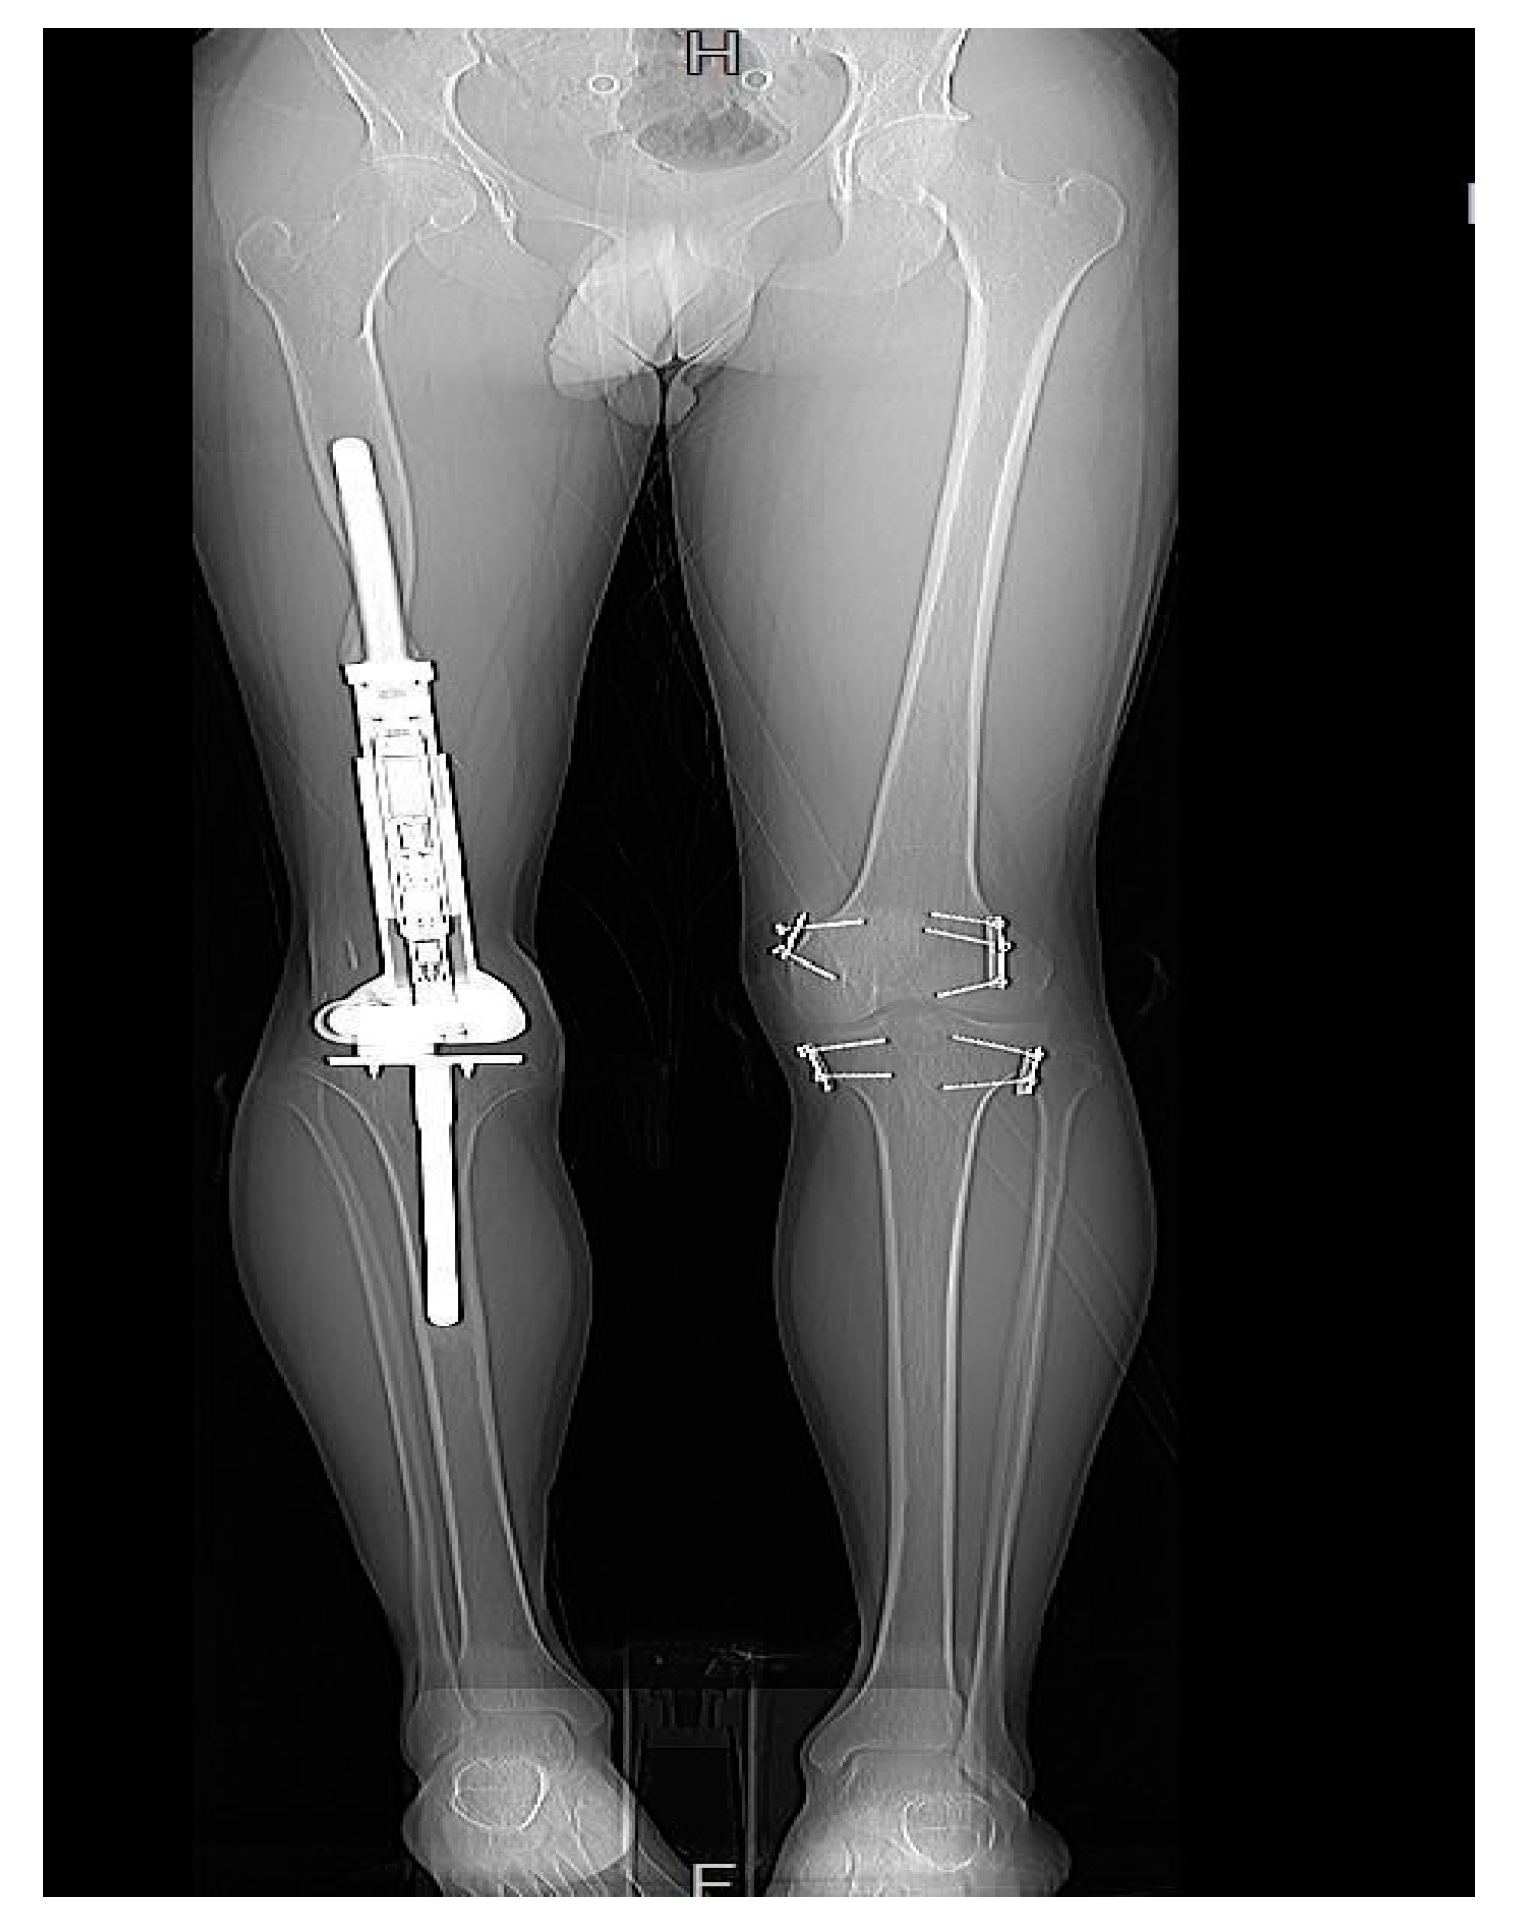

3.6. Need for Further Management

Patients with rotational and angular deformities did not necessitate management, as the deformities were tolerated well. Moreover, patients with an LLD of less than 10 mm demanded no further management. An LLD between 10 and 20 mm was managed solely by a shoe lift. However, an LLD of >20 mm, was treated on a case-by-case basis. Two patients required operative revision and serial elongation due to the anticipated growth potential of the contralateral leg. The remaining two patients were managed using epiphysiodesis of the contralateral distal femur and proximal tibia (Figure 7).

Figure 7. Patient 3 had undergone EDFE using MUTARS® Xpand. However, due to an LLD of 37 mm, this patient required epiphysiodesis of the contralateral limb.